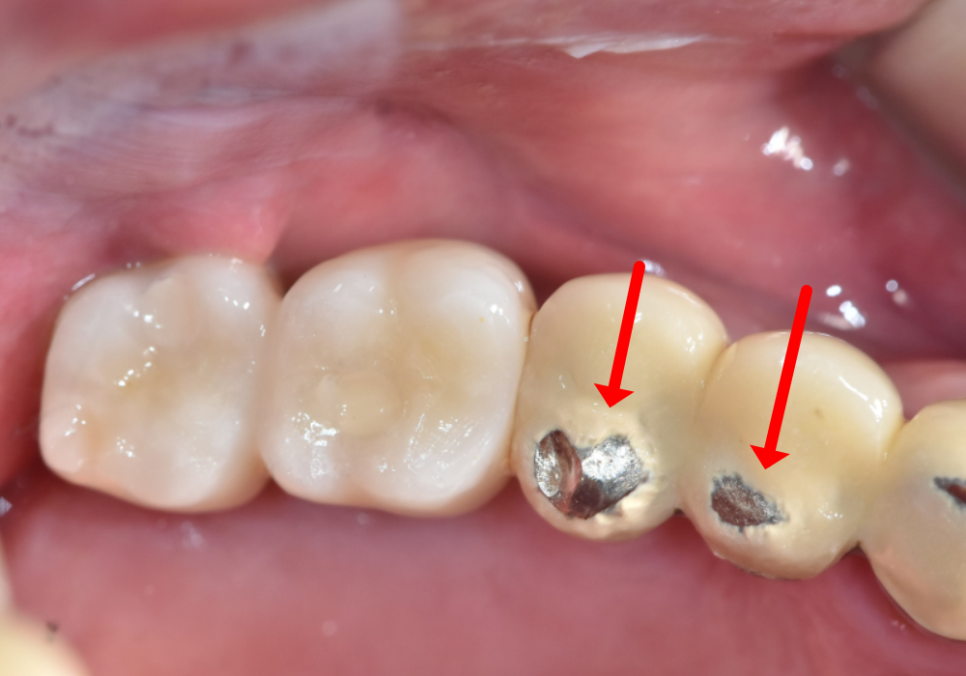

SCRP 타입이 아닌 CEMENT 타입?

고덕 치과, 임플란트가 흔들려요. 뽑아야 할까 봐 고민이라면?

그런데,

여기서 예상치 못한 난관에 부딪혔습니다.

환자분의 기존 보철물이

'시멘트(Cement) 타입'이었기 때문입니다.

임플란트 보철을 만드는 방식은

크게 두 가지가 있는데,

이 둘은 유지 보수 면에서 큰 차이가 있습니다.

조금 더 자세히 비교해 드릴게요.

① 시멘트 타입 (Cement Type)

마치 자연치아처럼 뚜껑을 덮고,

치과용 강력 접착제로 '딱' 붙여버리는 방식입니다.

장점 : 나사 구멍이 없어서 외관상 아주 깔끔하고 예쁩니다. 씹는 면이 매끈해서 음식물이 끼거나 걸리는 느낌도 덜하죠.

단점 : 수리가 매우 어렵습니다. 숨겨진 나사 구멍을 찾느라 멀쩡한 보철을 뚫어야 하거나, 최악의 경우 보철물을 통째로 뜯어내야 합니다.

안타깝게도 환자분은

'문'이 없는 1번(시멘트 타입)이었습니다.

단단한 도자기를 무리해서

뚫다간 보철만 망가지고

환자분 고생만 길어지기에,

결국 상의 끝에 기존 보철을 뜯어내기로

결정했습니다.

240614